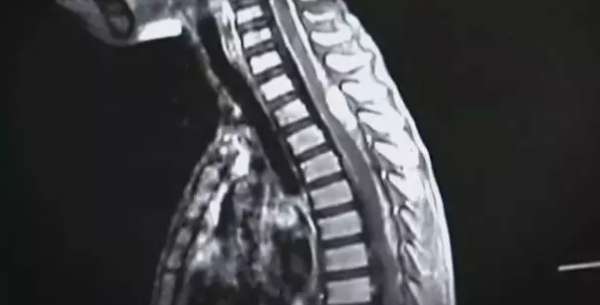

髓母细胞瘤,这是轩轩所患疾病的医学名称,这是一种目前全世界都尚无法根治的恶性肿瘤,主要发生于14岁以下的儿童。

现在,轩轩虽然脑瘤已经切除,但病情已经扩散到脊柱,因此放疗和化疗成了家常便饭。